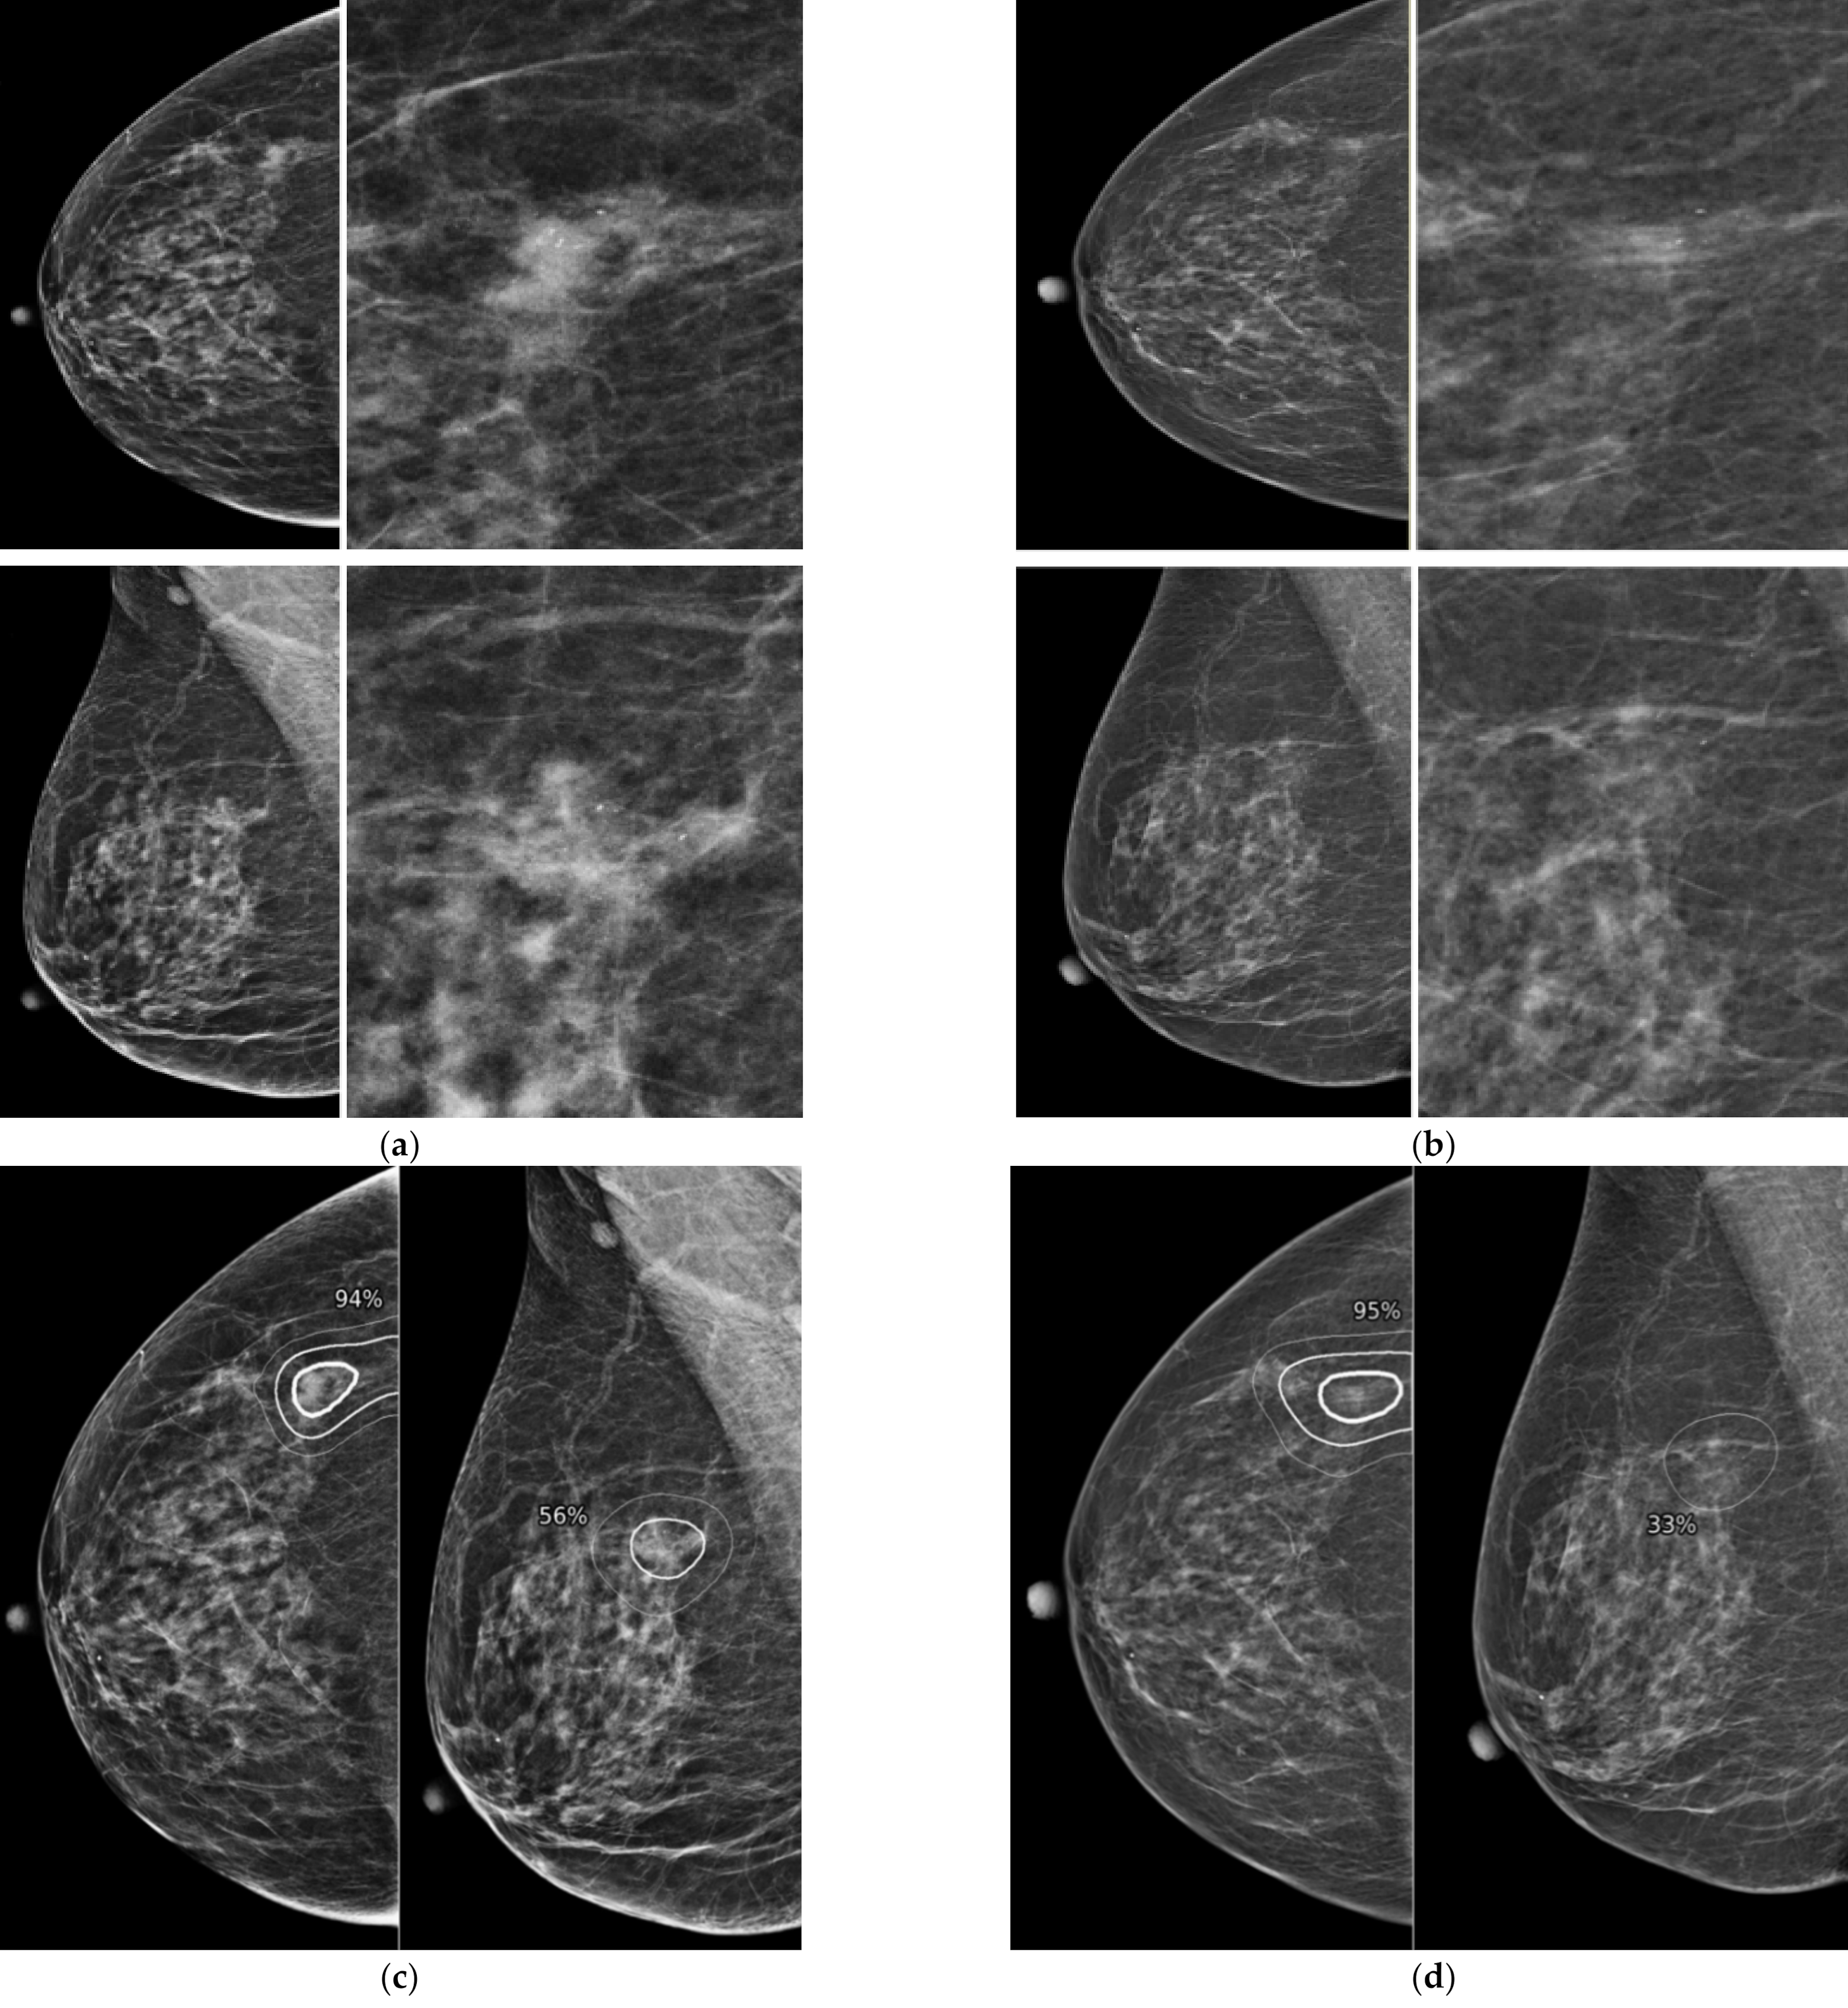

Figure 2.

Representative case of missed cancer detected by AI-CAD. A 67-year-old woman had a focal asymmetry with increased number of calcifications in diagnostic mammogram (a). After biopsy, this lesion was confirmed as invasive carcinoma. When the two radiologists reviewed the prior mammogram performed 12 months ago (b), asymmetry visible on CC view and several calcifications were retrospectively detected at the same location. When the AI-CAD was retrospectively applied, the AI-CAD identified the exact location of lesion in the diagnostic mammogram (c) and prior mammogram (d).